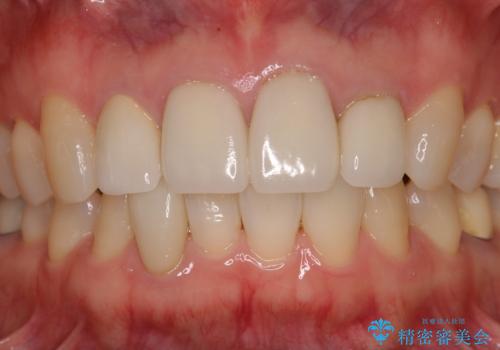

クラウンの種類は異なりますが、色調の適合したクラウンを装着することができました。